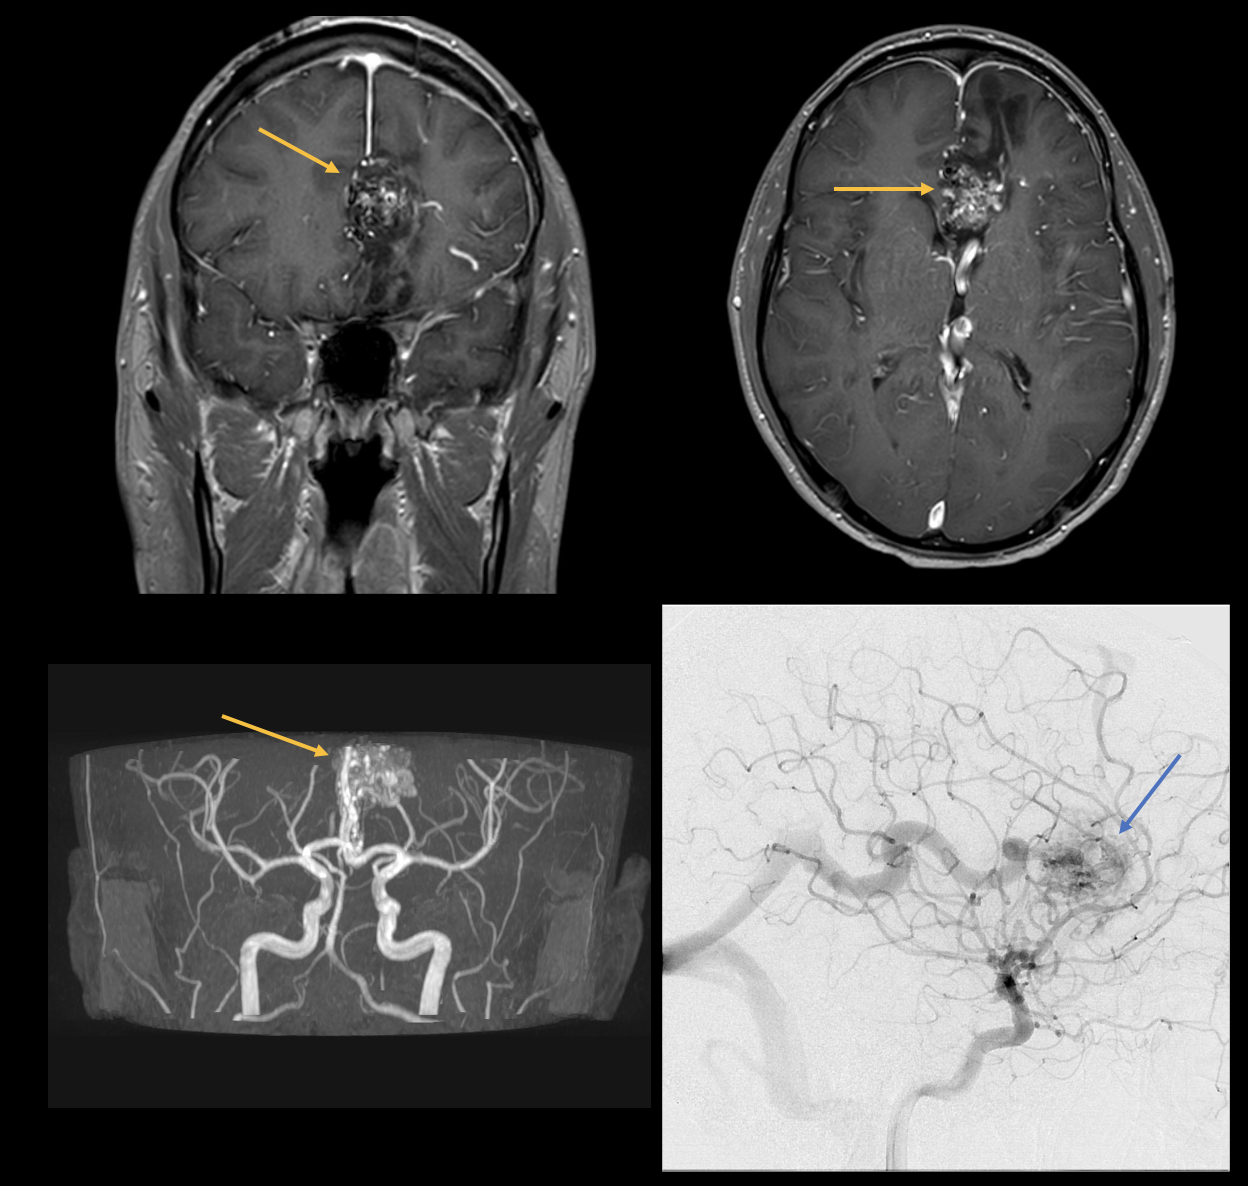

Il mal di testa è una delle sindromi dolorose più comuni con cui i medici si confrontano nella pratica clinica quotidiana. Si distingue tra cefalea primaria (ad esempio, emicrania) e secondaria (ad esempio, dopo un trauma cranio-cerebrale o causata da infezioni). Le immagini seguenti mostrano un paziente ricoverato in ospedale con una forte cefalea e nausea. La risonanza magnetica e l'angiografia mostrano una malformazione arterovenosa (MAV). Una MAV è una malformazione vascolare congenita con connessioni shunt (nidus) tra arterie e vene cerebrali senza un letto capillare intermedio. Le malformazioni artero-venose possono rimanere asintomatiche per tutta la vita. Tuttavia, spesso si manifestano con cefalee tra i 20 e i 40 anni. Le emorragie intracraniche si verificano in circa il 50-60% dei pazienti, le crisi epilettiche e i deficit neurologici focali in circa il 25% delle persone colpite. La terapia classica è la resezione chirurgica, anche se il trattamento endovascolare è sempre più utilizzato.

image4.png

Figura 4: Immagini di risonanza magnetica assiale e coronale e angiografia a sottrazione digitale che mostrano le connessioni dello shunt tra arterie e vene. Il nidus è contrassegnato dai pilastri.